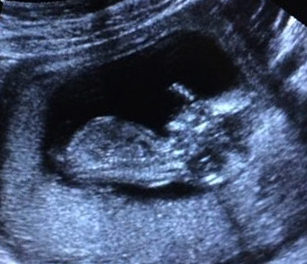

I'll add all of the photos I have. A leg isn't showing in the potty shot so I drew it in for a better idea. i just can't believe that this could be a boy - it looks nothing like any others I've seen. What are your thoughts? Would you announce going off of these images?

Attachment 28149Attachment 28153Attachment 28150Attachment 28151